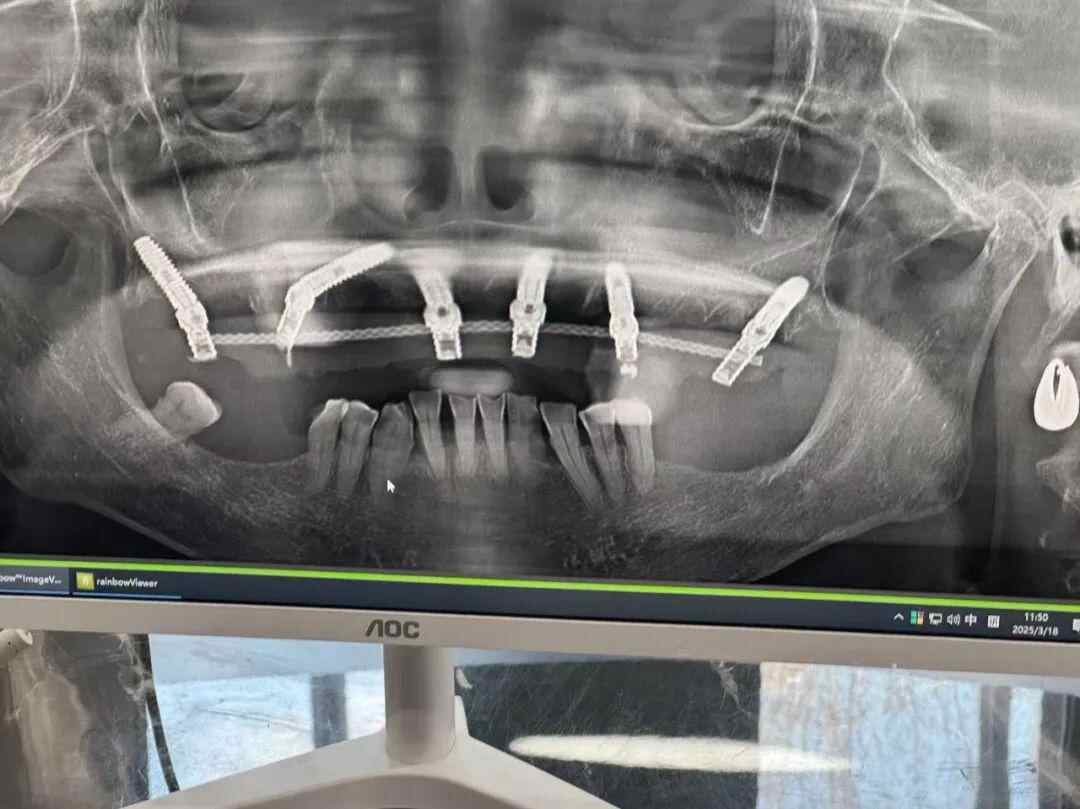

在老人“脑梗”治疗出院后,张先生等家属到“国颂口腔”询问过母亲种植牙治疗的过程,“当时是一个值班医生,调出了X光片,显示我母亲治疗前上牙有10颗牙,治疗后这些牙都没了,取而代之的是6个人工牙根。”

记者向“国颂口腔”了解情况时,工作人员证实,冯阿姨在该口腔医院治疗当天拔掉5个松动的牙和5个牙根,之后“即拔即种”了6个人工牙根。工作人员强调,“这种半口种植的操作呢,这是一个非常常规的,拔牙后种植也是常见的医疗行为。”